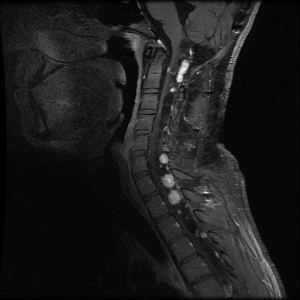

Hemangioblastomas de cerebelo y médula espinal

Los hemangioblastomas son la manifestación más común en los pacientes con enfermedad de VHL y afectan a más del 70 % de las personas. En un estudio prospectivo se evaluó la evolución natural del los hemangioblastomas.[16] La media de edad de aparición de los hemangioblastomas del sistema nervioso central (SNC) es de 29,1 años (intervalo, 7–73 años).[17] Los hemangioblastomas del SNC se observaron con mayor frecuencia en el cerebelo (45 %), la médula espinal (36 %), la cola de caballo (11 %) y el tronco encefálico (7 %).[18] Aunque los hemangioblastomas esporádicos son casi siempre solitarios por naturaleza, las lesiones en el SNC asociadas a la enfermedad de VHL a menudo son multifocales. Luego de una media de seguimiento de 7 años, el 72 % de 225 pacientes estudiados presentaron lesiones nuevas.[18] En las figuras 2 y 3 se muestran hemangioblastomas de cerebelo y médula espinal, respectivamente, en pacientes con enfermedad de VHL.

En la imagen se observan tres paneles. En el panel de la izquierda se muestra una vista sagital de dos lesiones prominentes de color claro en el tronco encefálico y el cerebelo. En el panel del medio se muestra una vista axial de una lesión prominente en el tronco encefálico. En el panel de la derecha se muestra una vista axial de una lesión en el cerebelo con un componente quístico que se ve como un área grande y oscura.

Vista sagital del cuello donde se observan varias lesiones de color claro en la médula espinal.